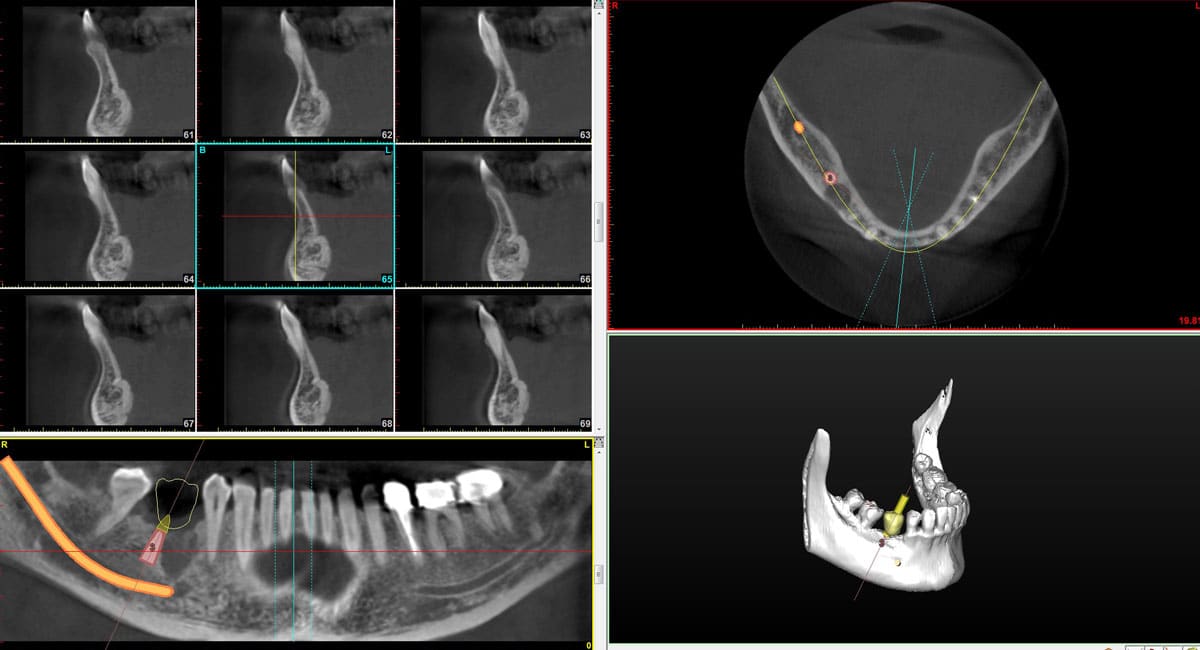

3D Cone Beam X‐Rays

The 3D Cone Beam imaging system allows our practice to generate accurate 3D imagery of your jaw, mouth and teeth with much more detail than traditional x-rays. This technology also allows us to measure bone density, which is essential for placing dental implants. With CBCT, we’re able to build more precise treatment plans, yielding improved patient outcomes and more predictable results.

Digital dental implants refers to a type of treatment plan that simulates dental implant surgery using computer software. Planning your dental implant surgery with 3D imaging and computer models means we can determine the precise location and angle for each dental implant to optimize your outcome.